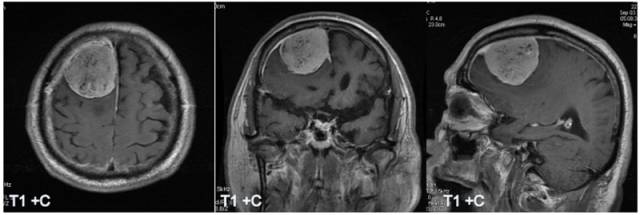

病例一:男性,83岁,头痛

病理:混合型脑膜瘤

T1、T2显示鞍区实质性等信号肿块,垂体柄受压紧贴视交叉膈面。增强呈明显均匀强化,动态增强信号强度表现为早期快速升高,中后期缓慢下降。

HE染色示:过度型脑膜瘤(同时含有上皮型脑膜瘤和纤维性脑膜瘤的病理特点),可见椭圆形及细长形肿瘤细胞,细胞边界不清,胶质纤维较少。